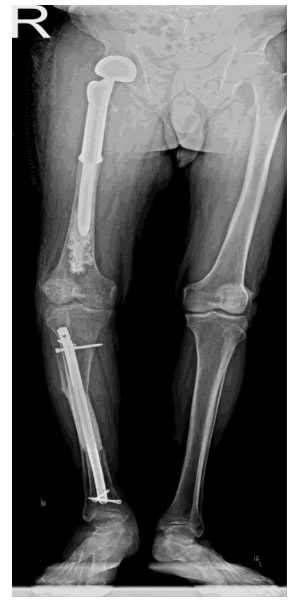

CASE 52: A patient underwent surgery due to the risk of fracture caused by metastasis of thyroid cancer to the right tibia.

Post-surgery: The X-ray shows a cemented tumor prosthesis applied to the upper end of the right femur, and cementation and closed pinning procedures performed on the tibia.